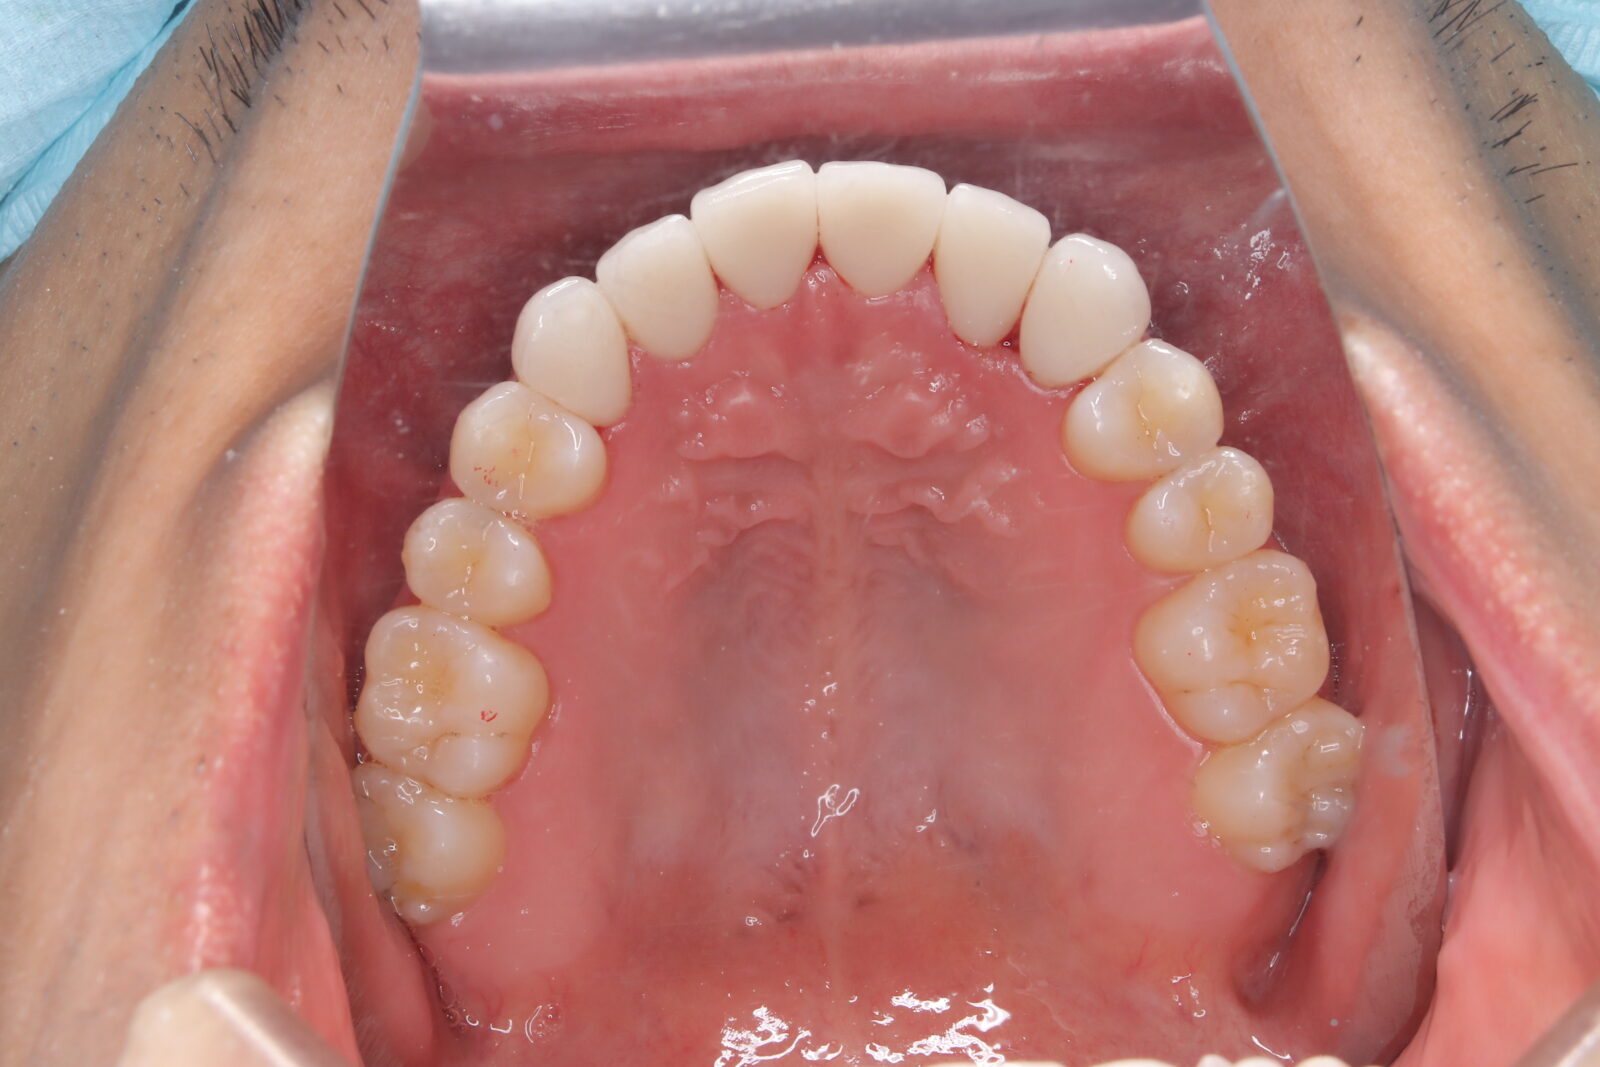

インビザライン(全体矯正)+ホワイトニングコースの症例

典型的な出っ歯だったが、インビザラインとホワイトニングでコンプレックスを改善。

・費用:935,000円(税込)

・治療期間:14ヶ月

・通院回数:14回

・34歳女性

-リスクと副作用-

・長時間マウスピースを装着するため、むし歯や歯周病のリスクがある。治療後はリテーナーを装着しないと後戻りしてしまうリスクがある。

・ホワイトニング剤の影響で知覚過敏が起こる可能性がある。色が徐々に戻る可能性がる。